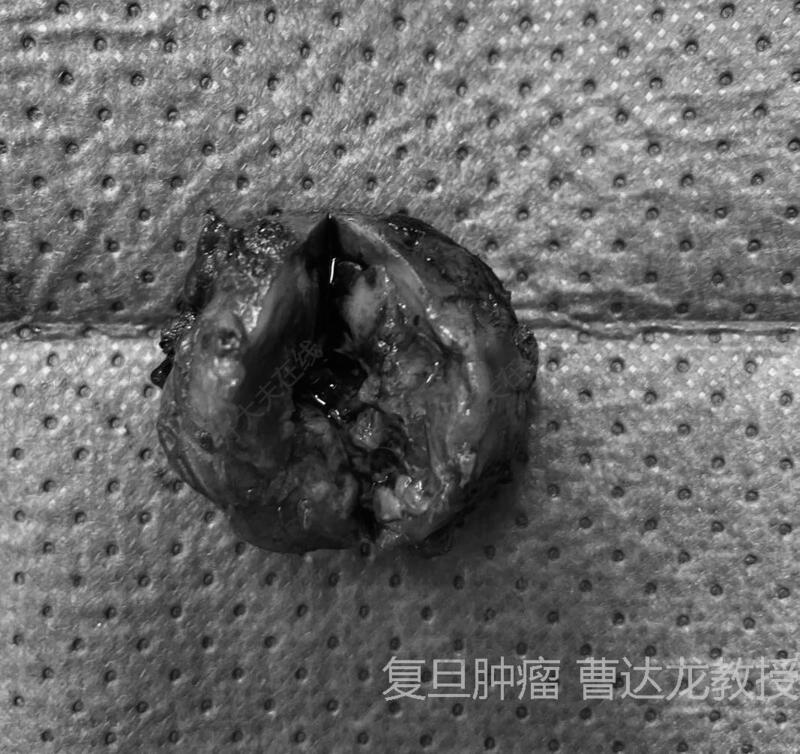

治疗中

顺利为该患者实行了机器人辅助肾部分切除术,为患者完整切除了肿瘤,同时成功为患者保住了肾脏!